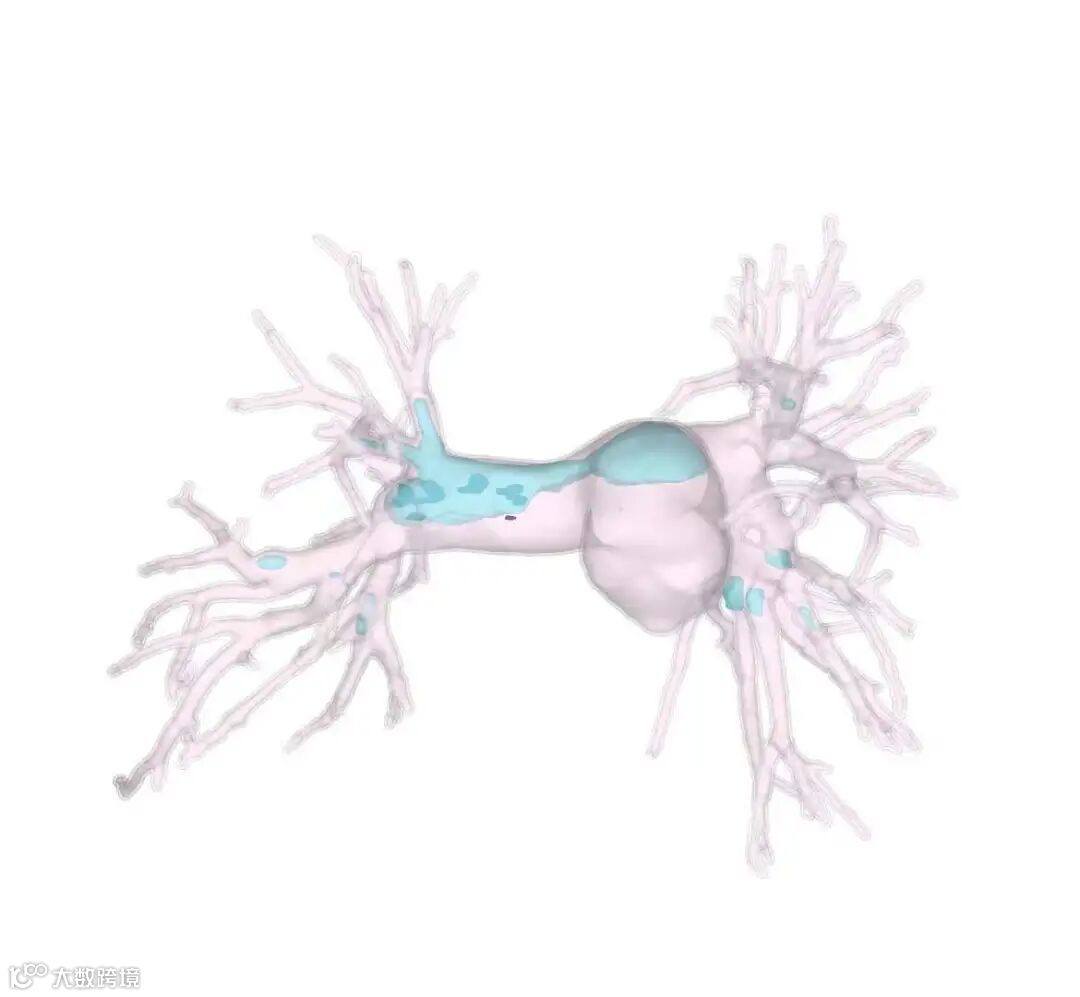

考虑患者情况特殊,血栓分布较广,血管外科团队术前采用思源智慧医疗3D打印模型,观察血栓的分布情况,对手术进行规划。降低了手术时间,减少了手术风险,最终手术圆满成功!家属激动地说:“是厦心医院给了他第二次生命”。

思源智慧医疗术前肺动脉数字模型